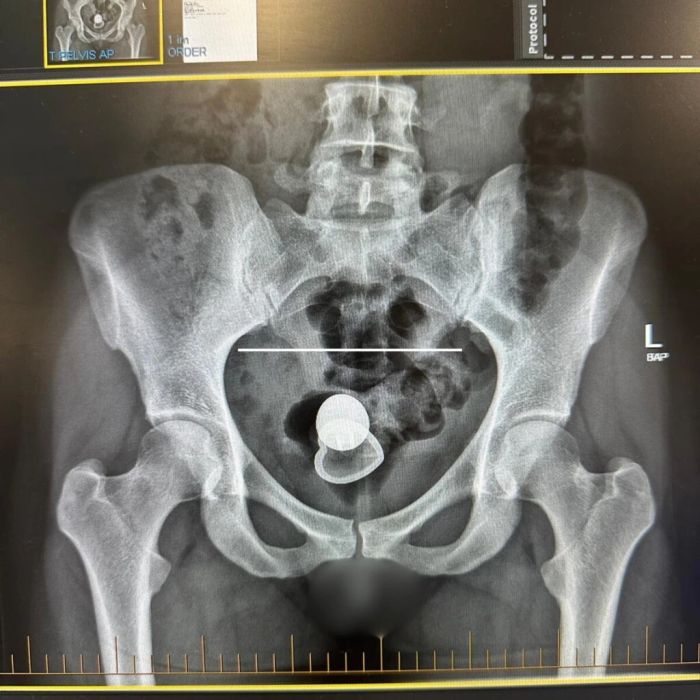

Они с любовником начали искать секс-игрушку по всей комнате, однако не нашли. Тогда женщина провела «внутренний осмотр» и обнаружила пробку внутри себя. Дэвис попыталась вытащить ее самостоятельно, но не смогла. Пришлось обратиться в клинику. «В больнице еще два человека пытались достать ее, но ничего не вышло»,

В итоге ей пришлось ждать два дня, прежде чем врачи провели операцию под общим наркозом. Извлечение секс-игрушки заняло пять минут. Врачи предложили ей взять пробку на память, но она решила выкинуть ее, потому что «у нее есть еще».